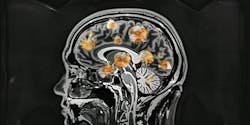

A new study has connected stages III and IV chronic traumatic encephalopathy (CTE) to a higher risk of dementia, according to the study’s funder, the National Institutes of Health (NIH). Key findings are summarized in a press release.

The analysis was conducted by Boston University CTE Center and the U.S. Department of Veterans Affairs Boston Healthcare System researchers using 614 brains that were donated by individuals who experienced repetitive head impacts while alive, the cause of CTE. It is important to note that Alzheimer’s disease, Lewy body disease, and frontotemporal lobar degeneration were not present in any of the brains.

While examining the brains, the scientists discovered that those “with stage IV CTE were 4.5 times more likely to have had dementia during life than donors without CTE.” Additionally, donors with stages I and II CTE were found to not have an increased risk of dementia or cognitive impairment and functional decline, while “mood and behavioral symptoms were not observed at any stage of CTE.”